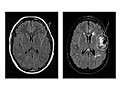

Magnetic resonance imaging (MRI) of the head

Normal:

All structures of the head—the brain, its vessels, spaces, nerves, and surrounding structures—are normal.

No abnormal growths, such as tumours, in or around the brain are present.

No bleeding, abnormal blood vessels (AV malformations), abnormal pockets of fluid, blockage in the flow of blood, or bulges in the blood vessels (aneurysm) are present.

No signs of infection or inflammatory disease, such as encephalitis or meningitis, are present.

Abnormal:

Tumours in the brain or in areas outside the brain, such as an acoustic neuroma, are present.

Bleeding or swelling (edema) in or around the brain is present.

Areas of infection or inflammatory disease, such as encephalitis or meningitis, are present.

Abnormal areas in the brain may mean that certain diseases, such as Huntington's disease, multiple sclerosis, Parkinson's disease, or Alzheimer's disease, are present.

Bulges or weak areas (aneurysms) or abnormal blood vessels (such as an AV malformation) are present.